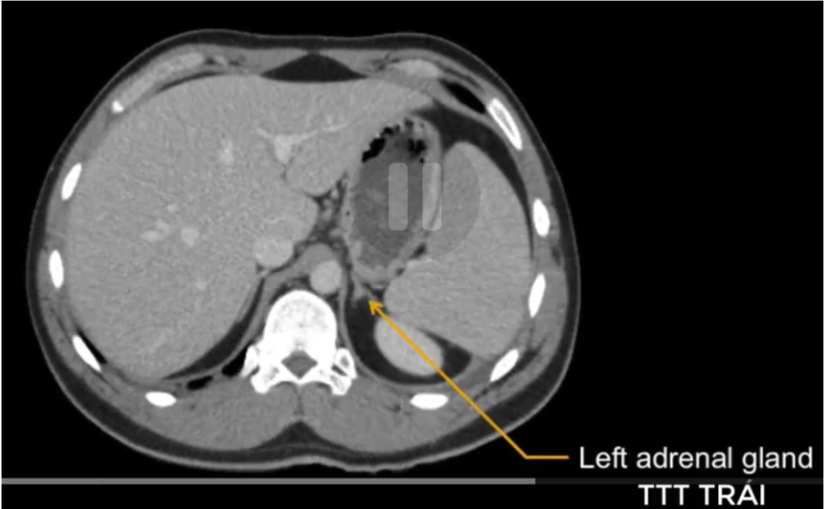

cq trong hình ?